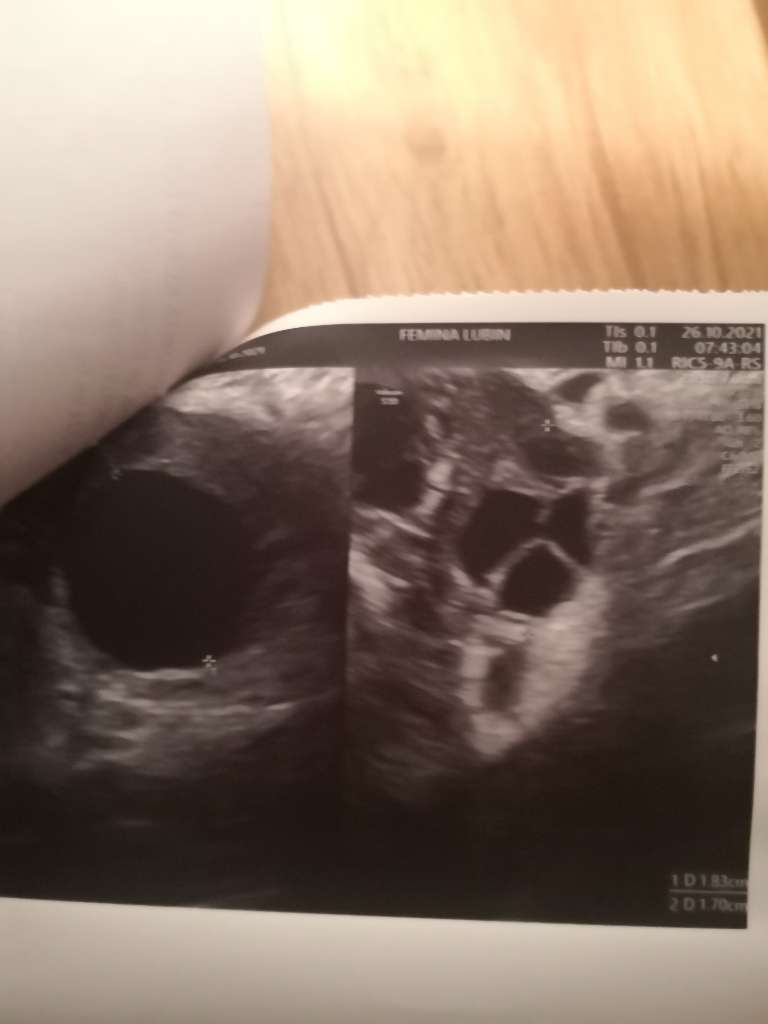

Jezu laski ale każda kobieta ma te czarne kropki na jajnikach (pecherzyki). Jedna ma ich mniej druga więcej i dopóki np nie tworzą koralików dookoła to jest OK. To nie jest tak że bez pcos jest ich 1-2 sztuki. Jest ich mniej ale jednak zazwyczaj występują w liczbie mnogiej.

Wydaje mi się ze te pecherzyki ułożone obwodowo (typowy obraz dla PCO) to taki trochę egzotyczny widok [emoji23] ja mam jeden jajnik wyglądający trochę na PCO (właśnie z uwagi na ułożenie pęcherzyków), ale i badania hormonalne są ok, i owulacje się odbywają, nie mam innych niepokojących objawów wiec po prostu taki se ten jajnik jest. Mniej go lubię, ale jest [emoji16] normalnie te pecherzyki nie są tak ułożone jak korale i może jest ich nieco mniej to i może widok jest mniej szokujący. Mi ostatnio lekarz pokazał bardzo dokładnie ten mój lepszy jajnik tuż po okresie i w sumie to wyglądało to niezachecajaco na moje laickie oko [emoji23]

Gdzieś kiedys czytałam ze najlepiej oglądać pecherzyki antralne na początku cyklu i ze powinno być ich nie mniej niż 5, kilka do kilkunastu. No ale mało kto robi usg podczas okresu [emoji23]

Ja mam takie zdjęcia 🤣 Wiedziałam, że to pęcherzyki, ale nie miałam pojęcia, że ich ułożenie czy ilość mogą wskazywać na pcos 🙆‍♀️